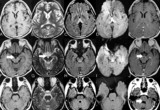

코돈129번 MM형의 문제

- 2012-03-25 22:03

- 양기화 의학박사

한국인은 광우병에 잘 걸리는 체질이다?

- 2012-03-17 19:43

- 양기화 의학박사

현지 언론에서 아레사 빈슨 사인을 CJD, vCJD로 의심한 이유

- 2012-02-19 18:17

- 양기화 의학박사

편향적으로 추정된 아레사 빈슨의 사인

- 2012-02-05 17:41

- 양기화 의학박사

급성 베르니케병으로 추정되는 아레사 빈슨의 사인

- 2012-01-28 22:09

- 양기화 의학박사

과학적으로 추정해본 아레사 빈슨 죽음의 원인

- 2012-01-28 21:18

- 양기화 의학박사

방송이 만들어낸 고(故) 아레사 빈슨의 사인

- 2012-01-14 22:56

- 양기화 의학박사

고(故) 아레사 빈슨양이 인간광우병으로 사망했다?

- 2012-01-14 22:56

- 양기화 의학박사